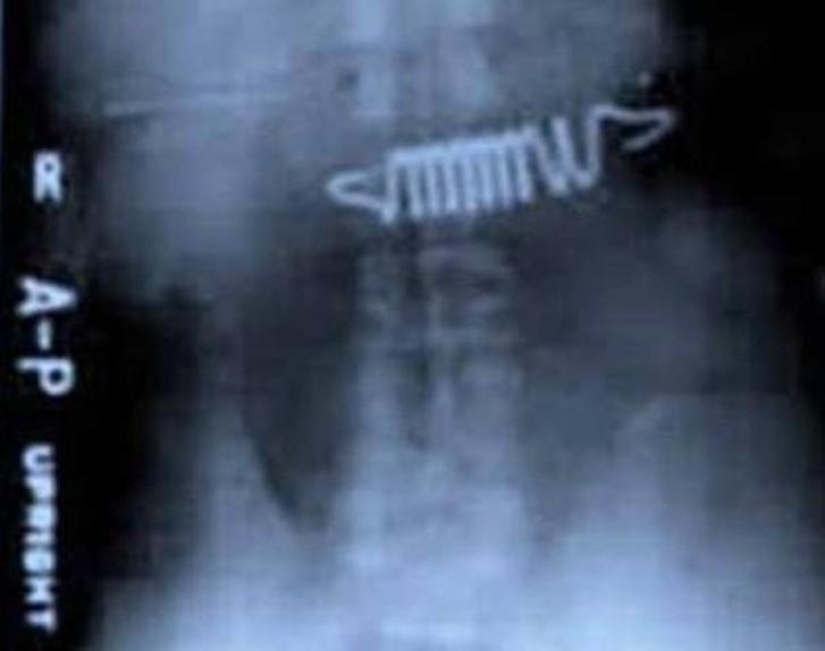

19. Springs from the bed.